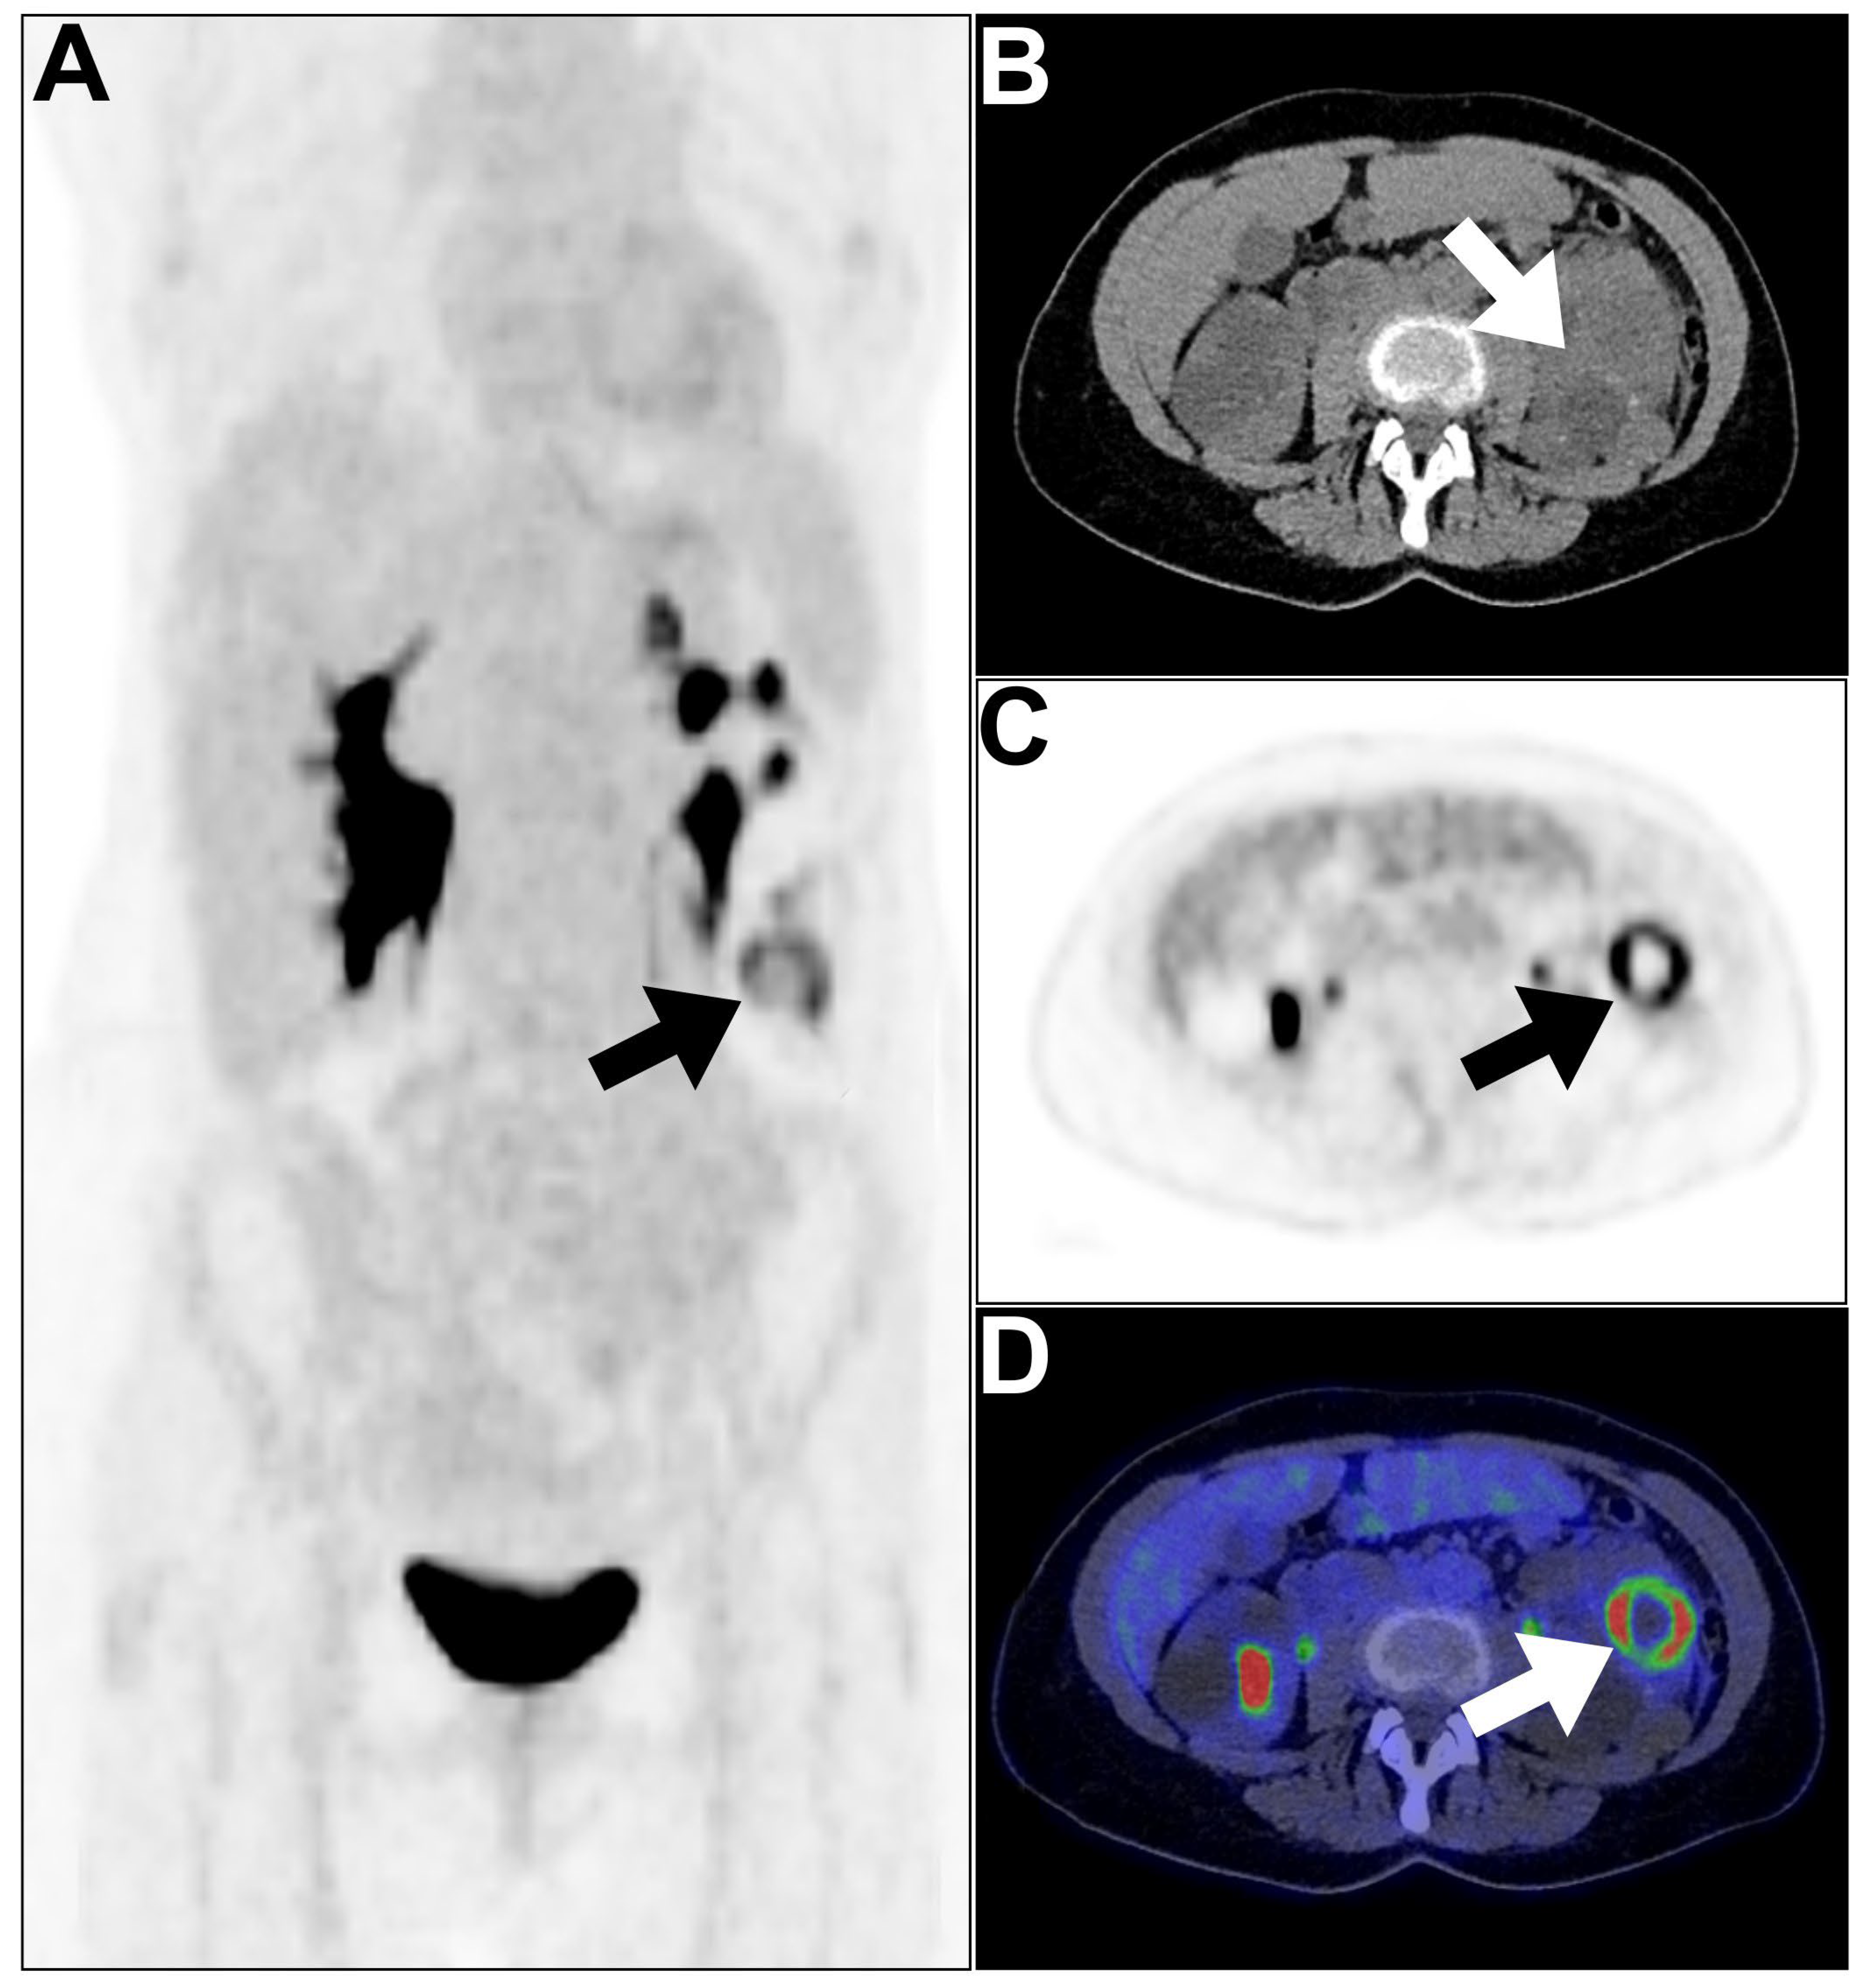

- Zhou, Y.; Yang, X.; Liu, H.; Luo, W.; Liu, H.; Lv, T.; Wang, J.; Qin, J.; Ou, S.; Chen, Y. Value of [68 Ga] Ga-FAPI-04 imaging in the diagnosis of renal fibrosis. Eur. J. Nucl. Med. Mol. Imaging 2021, 48, 3493–3501. [Google Scholar] [CrossRef] [PubMed]

- Conen, P.; Pennetta, F.; Dendl, K.; Hertel, F.; Vogg, A.; Haberkorn, U.; Giesel, F.L.; Mottaghy, F.M. [68 Ga] Ga-FAPI uptake correlates with the state of chronic kidney disease. Eur. J. Nucl. Med. Mol. Imaging 2022, 49, 3365–3372. [Google Scholar] [CrossRef] [PubMed]

| Chronic pyelonephritis | 68Ga-FAPI | Persistent, patchy increased uptake, indicating chronic inflammation |